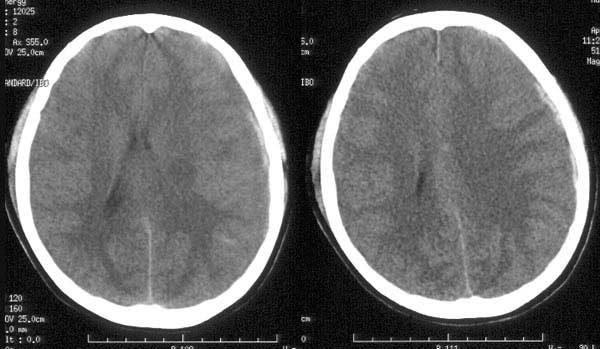

患者入院后予脱水治疗,并于10小时后行ct复查:

ct诊断:1、左颞硬膜下血肿已吸收消失。

2、蛛网膜下腔出血量较前增多。

3、脑肿胀程度较前明显改善。